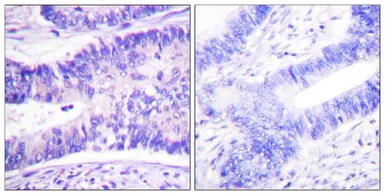

IHC-P analysis of human colon carcinoma tissue using GTX55451 WAVE1 (phospho Tyr125) antibody.

Left : Primary antibody

Right : Primary antibody pre-incubated with the antigen specific peptide